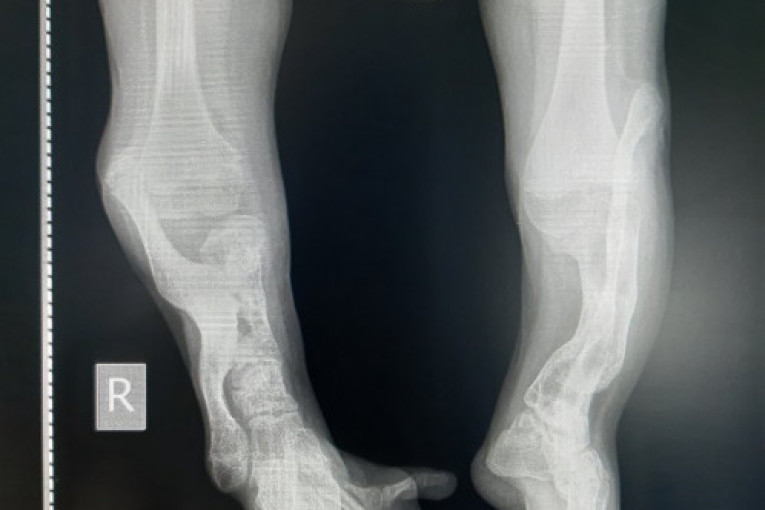

Mala Andreja iz Niša ima samo 14 godina, a operisana je čak 25 puta. Ona je jedna u milion dece koje se rodi bez potkoleničnih kostiju. Zbog  zdravstvenog problema mora da se služi kolicima i štakama, ne može samostalno da hoda i stalno je u bolovima.

Snimak Andrejinih nogu

Andreja ide u prvi razred srednje Umetničke škole. Ima 14 godina i rođena je bez potkoleničnih kostiju. Do sada je tri puta išla u Rusiju, a Goran i ona su tamo boravili po nekoliko meseci, jer je prema njegovim rečima, Andreja imala i po 10 hirurških zahvata zaredom. Ciklus oporavka nakon operacija je dug i bolan, a operacije i boravak u Rusiji izuzetno skupi. Andreja će morati da se podvrgne ovim zahvatima u Rusiji još nekoliko puta, jer , kako Goran kaže, „tek su na početku“.